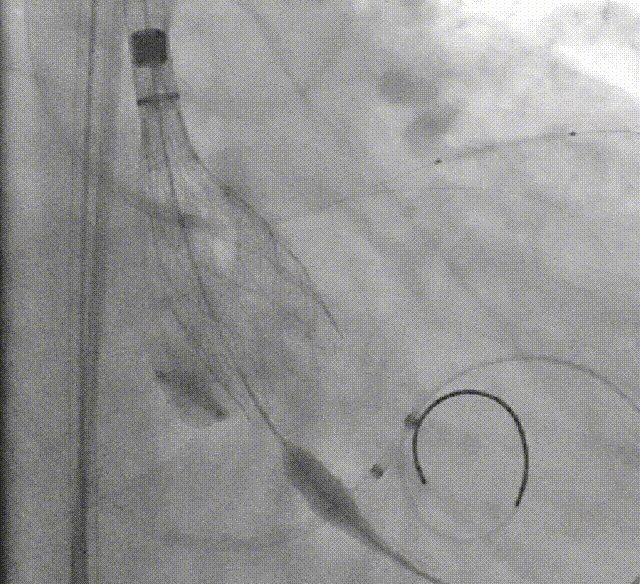

术者采用患者右侧主入路,顺利完成导丝和猪尾跨瓣等准备工作。进Landerquist超硬导丝,采用25mm球囊进行预扩,仔细评估冠脉风险后,决定对冠脉采取保护措施。根据球囊扩张情况,术中决定使用金仕生物的ProStyle预装干瓣TAV32。打开包装后,很迅速的完成了瓣膜和系统植入前的准备。输送过程系统和瓣膜轻松过弓并顺利跨瓣;开始初步释放,然后快速起搏下释放,发现位置略高后进行回收,重新定位后最终成功完成释放。反复造影发现冠脉存在阻塞风险,武汉协和团队按照风险预案在左冠植入4.0*18mm支架进行保护。术后显示左右冠脉血液灌注通畅,术后超声测量峰值流速1.45m/s,峰值压差8mmHg,几乎无瓣周漏。入路闭合顺利,无心脏及血管并发症,手术成功。

球囊扩张

初步释放

再回收后释放,术中冠脉评估

系统撤出

支架植入